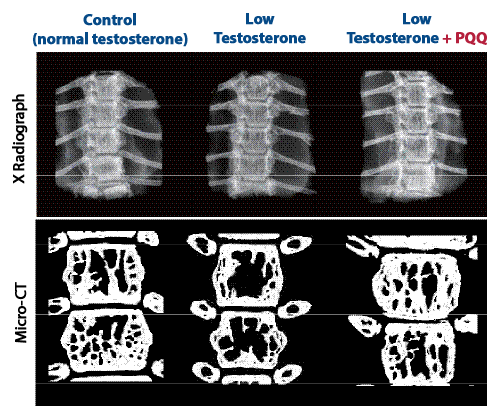

To evaluate the impact of PQQ on bone health, researchers utilized X-ray and CT scan imaging of the bones of all three groups of mice.

Images of control mice with normal, youthful testosterone levels revealed normal bone-mineral density and volume.

For the low-testosterone mice not treated with PQQ resembling the situation frequently seen in older men with declining testosterone, images show profound bone mineral and volume loss.6

But the images of the low-testosterone mice supplemented with PQQ reveal something remarkable: bone-mineral density and volume was significantly greater than the untreated low-testosterone mice—and their bone density was similar to those of the healthy mice with youthful testosterone levels.

Images by X-ray (top) and micro-CT scan (bottom) show vertebral bone density and volume in control (normal-testosterone) mice (left), in low-testosterone mice without supplementation (middle), and low-testosterone mice supplemented with PQQ (right). The control group is normal and healthy, while images of low-testosterone mice show dramatic bone structure deterioration. Images of low-testosterone mice supplemented with PQQ show mineralization more like that in the control group, compared with the unsupplemented low-testosterone mice.6